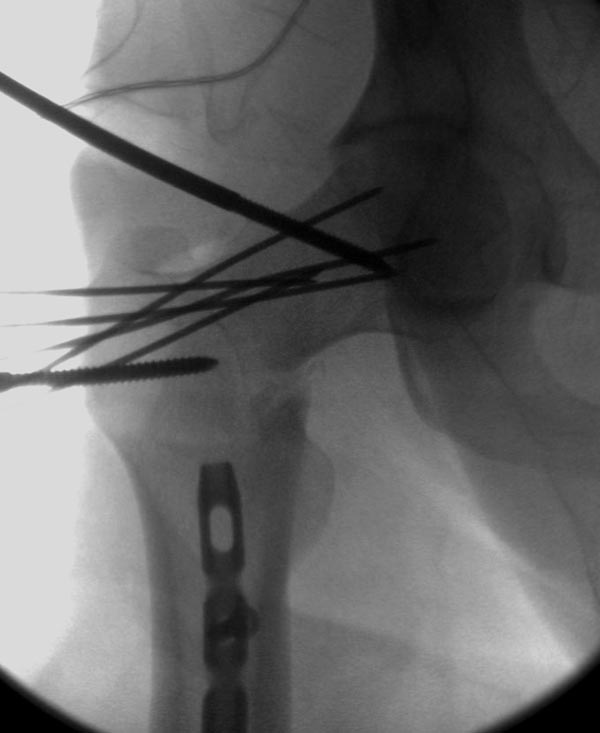

Здесь выставлен ренгенограммы больного, ему 21, травму получил в

результате высокоскоростной погони на украденной машине, которая

закончилась смертью трех остальных“боевых комрадов”. Начатую коллегой

открытую операцию на шейке пришлось закончить мне, установкой винтов и

ретроградной фиксацией бедра. Выписка в обычное сроки и наблюдался

амбулаторно. Каждый раз напоминали о возможности осложнений ввиде

несращения! По истечению 4 месяцев появились признаки варусной

деформации. На СТ срезах несращение шейки и бедра. Риминг, замена на

более толстый гвоздь и вальгусная остеотомия.